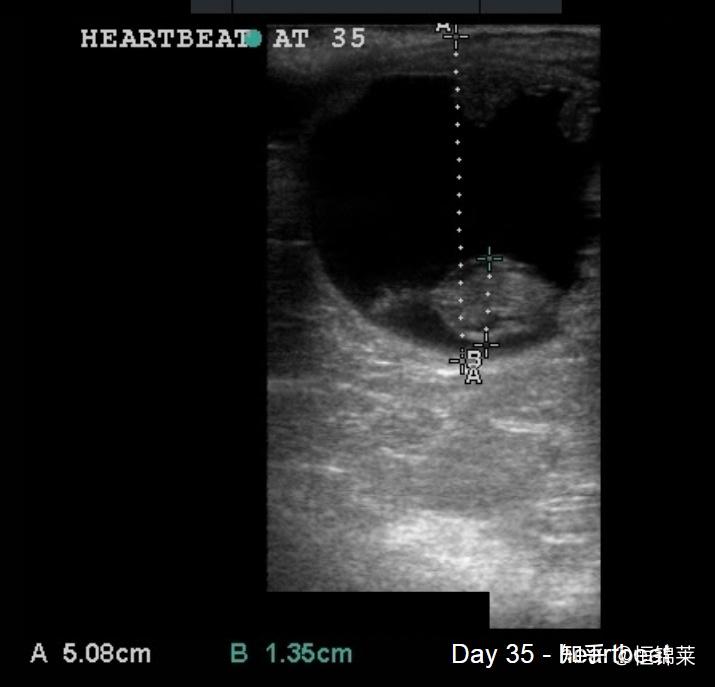

在对母马进行超声检查以检测怀孕期间,我们将寻找胚胎囊泡。这是在超声屏幕上看到的黑色球体,代表早期胚胎内的液体和胚胎和/或胎儿周围发育中的胎盘内的液体。您可以在下方看到第 12 天和第 19 天母马的超声波扫描结果。注意囊泡的形状是如何变化的。

马妊娠35天超声图像